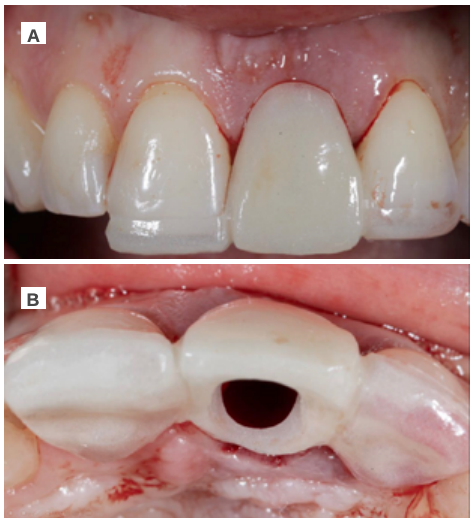

Under local anaesthesia (articaine 4% 1:100,000 adrenaline) with an infiltrative technique at the level of the vestibular fundus of the maxillary anterior region (anterior superior alveolar nerve) and palatine region (nasopalatine nerve), the coronal fragment of the ULCI was extracted before taking out its root (Figure 3A). A syndesmotomy of the surrounding soft tissue was performed for this, to establish the condition of the vestibular cortical bone by palpation. After that, the root was extracted in a controlled manner to minimise trauma, by first dislocating it with a periotome and subsequent controlled gripping with forceps (Figure 3B).

The provisional Maryland-type prosthesis was used as a provisional device and surgical guide to guarantee the correct vestibulo-lingual position of the OII, according to the plan devised, thus preventing any future problems at the prosthodontic level or in the integrity of the soft and hard tissues of the vestibular region (Figures 5A and 5B).